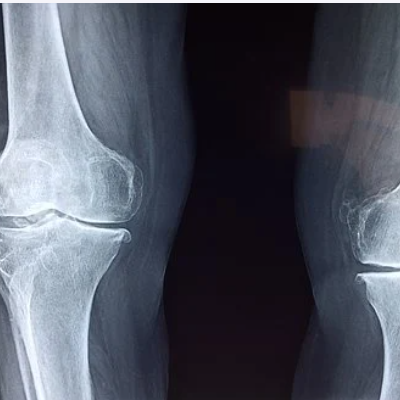

신체가 노화됨에 따라 무릎의 연골이 자연스럽게 마모되는 것으로 50세 이상의 사람들에게 흔할 수 있습니다.

류마티스 관절염

류마티스 관절염은 면역 체계가 무릎 관절포함 신체의 여러 관절을 공격하는자가 면역 질환입니다.

염증에 노출된 무릎은 붉은 붓기와 통증을 유발합니다. 류마티스 관절염으로 인한 무릎 통증은 운동으로 호전되는 경우도 있으니 정확한 진단후 무릎관리에 관한 운동을 해 주는 것이 좋습니다.